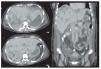

En todos los casos y después de una evaluación radiológica cuidadosa (Figuras 1 y 2), se determinó la necesidad de resección hepática de acuerdo con los siguientes criterios: a) presencia de colangitis refractaria a tratamiento médico con dilatación ductal segmentaria y/o abscesos colangíticos, b) falla en la resolución mediante manejo radiológico, c) falla transoperatoria para obtener un conducto adecuado para construir la anastomosis.

Figura 1. Tomografía computarizada de un paciente con lesión de vía biliar y arteria hepática derecha en la que se evidencian múltiples abscesos colangíticos en el lóbulo derecho del hígado.